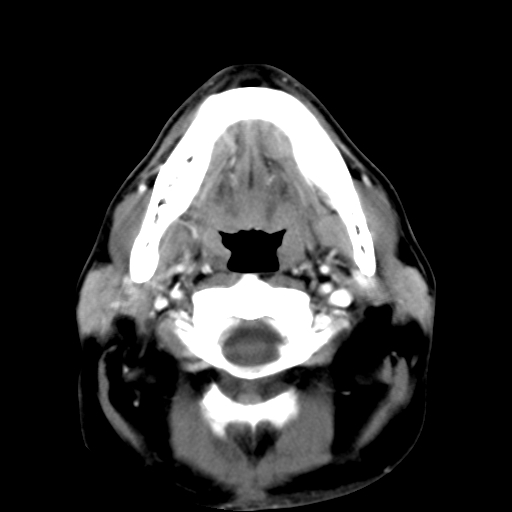

标题: CT24019:男,45岁,发现颈部肿物5个月。 [打印本页]

男,45岁,发现颈部肿物5个月,彩超示:双侧颈部及下颌部软组织增厚。

考虑双侧颈项部良性对称性脂肪增多症。